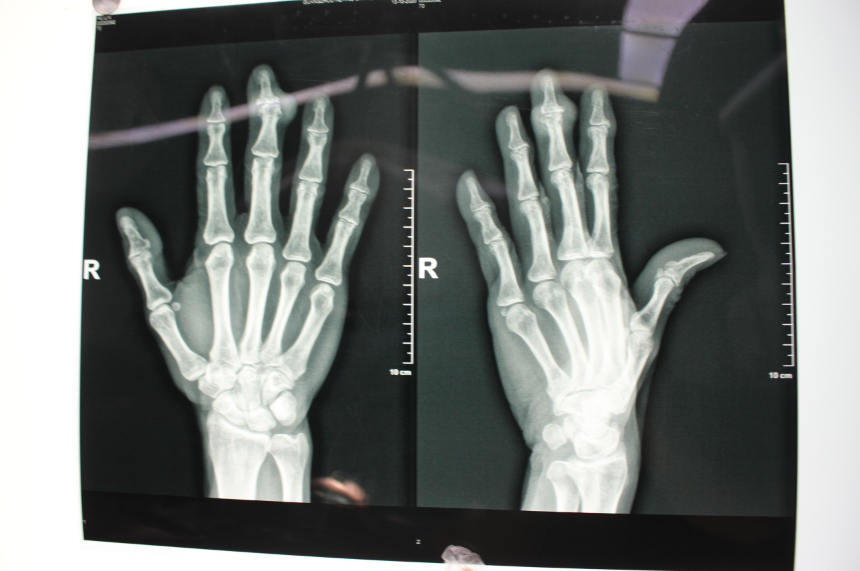

我院创伤显微手外科三区周洋医生透露,右中指远侧指间关节背侧可见明显肿物,大小约1cm*2cm,影响外观及右中指主动屈伸活动受限,检查片子显示患者右手环指末节指间关节半脱位,软组织肿胀,诊断为:右中指痛风结石,需要行痛风石切除术。

创伤显微手外科三区周洋等医生团队给张伯进行了痛风石切除手术,术中把患者的右中指切开,把痛风石切除,还进行了远指间关节融合和克氏针内固定(2枚),局部皮瓣修复。手术很顺利,术后肢体血运良好,接下来只需要控制及维持尿酸到正常水平即可逐渐康复。